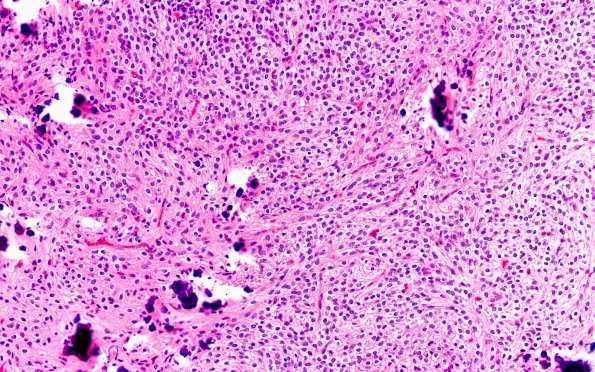

Washington University Experience | NEOPLASMS (NEURONAL) | Central Neurocytoma | 13B2 Central neurocytoma (Case 13) H&E 20X

H&E stained sections show a hypercellular neoplasm comprised of monotonous isomorphic sheets of tumor cells, demonstrating round-to-oval nuclei with smooth nuclear contours, fine chromatin and inconspicuous micronucleoli.